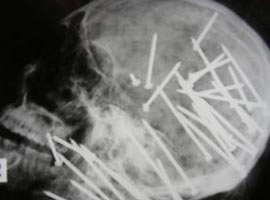

Polisin cesedini bataklıkta bulduğu bir adamın beynine 30'dan fazla çivi saplandığı ortaya çıktı.

Avustralya'da insanın kanını donduran bir cinayet işlendi. Avustralya polisi New South Wales bölgesinde bataklık arazide bir erkek cesedi buldu. Ceset üzerinde yapılan incelemede korkunç bir vahşet ortaya çıktı. Kimliği Chen Liu olarak açıklanan adamın kafasına çivi tabancasıyla defalarca sıkıldığı ortaya çıktı. Röntgende adamın beynine 30'dan fazla çivinin saplandığı görülüyor. Dedektif Mark Newman, Chen Liu'nun katillerini bulmak için geniş çaplı bir operasyon başlattıklarını söyledi.